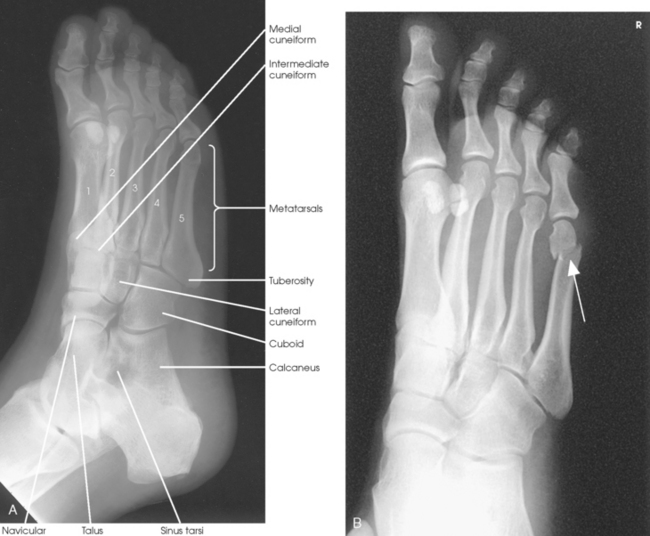

The foot consists of 26 bones (Figs. 6-1 and 6-2):

The bones of the foot are similar to the bones of the hand. Structural differences permit walking and support of the body’s weight. For descriptive purposes, the foot is sometimes divided into the forefoot, midfoot, and hindfoot. The forefoot includes the metatarsals and toes. The midfoot includes five tarsals—the cuneiforms, navicular, and cuboid bones. The hindfoot includes the talus and calcaneus. The bones of the foot are shaped and joined together to form a series of longitudinal and transverse arches. The longitudinal arch functions as a shock absorber to distribute the weight of the body in all directions, which permits smooth walking (see Fig. 6-2). The transverse arch runs from side to side and assists in supporting the longitudinal arch. The superior surface of the foot is termed the dorsum or dorsal surface, and the inferior, or posterior, aspect of the foot is termed the plantar surface.

The five metatarsals are numbered one to five beginning at the medial or great toe side of the foot. The metatarsals consist of a body and two articular ends. The expanded proximal end is called the base, and the small, rounded distal end is termed the head. The five heads form the “ball” of the foot. The first metatarsal is the shortest and thickest. The second metatarsal is the longest. The base of the fifth metatarsal contains a prominent tuberosity, which is a common site of fractures.

Beginning at the medial side of the foot, the cuneiforms are described as medial, intermediate, and lateral.

The cuboid bone lies on the lateral side of the foot between the calcaneus and the fourth and fifth metatarsals (see Fig. 6-1). The navicular bone lies on the medial side of the foot between the talus and the three cuneiforms. The cuneiforms lie at the central and medial aspect of the foot between the navicular bone and the first, second, and third metatarsals. The medial cuneiform is the largest of the three cuneiform bones, and the intermediate cuneiform is the smallest.